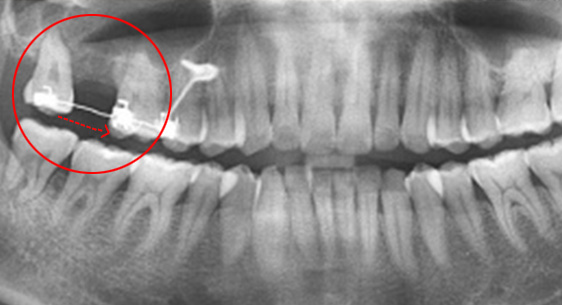

지속적인 통증과 잇몸염증

기존 포스트 제거 후 근관내 약재 삽입

재 신경치료(난이도 상)